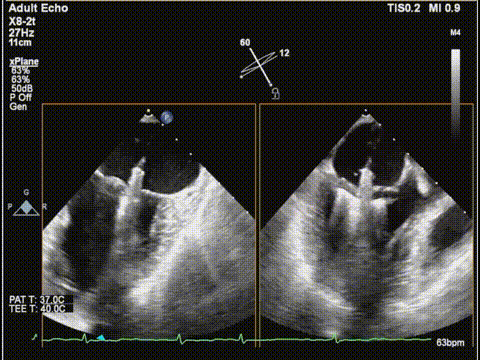

术前食道超声:

房颤,瓣环扩大的房性二尖瓣反流,反流主要集中在二区,二区后叶部分脱垂,后叶的长度16mm,前叶的长度是37mm。房间隔整体的条件可,从瓣环到拟定的卵圆窝顶部高度大概是41mm。

二尖瓣2区

二尖瓣2区color